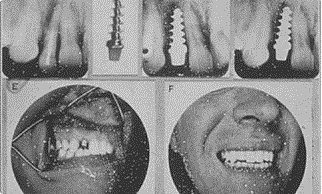

Estados Unidos Alvin Strock inserta el primer implante dental Vitallium.